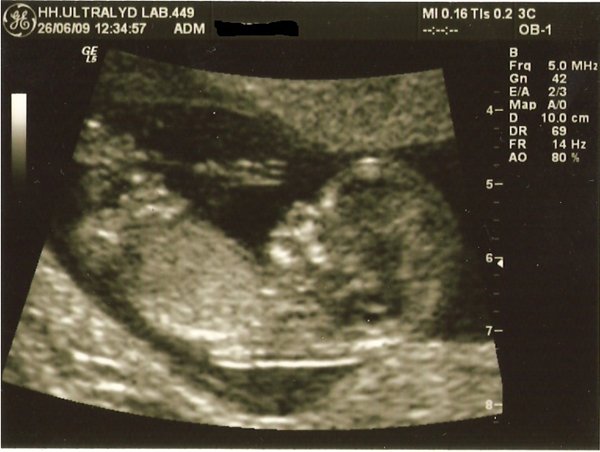

Jeg var til nf i dag! iih, hvor var det spændende og dejligt at se den lille.

Alt så fint ud og synes at billederne blev rigtig flotte

Terminen blev rykket et par dage fra 10.01.10 til 06.01.10, så er 12+2 uger henne

Vi har ikke fået svar fra doubletesten endnu, så har ikke fået endeligt svar.. Men udfra skanningen så alt fint ud, husker ikke helt, men det var ca. 1:5700, så det var SUPER.